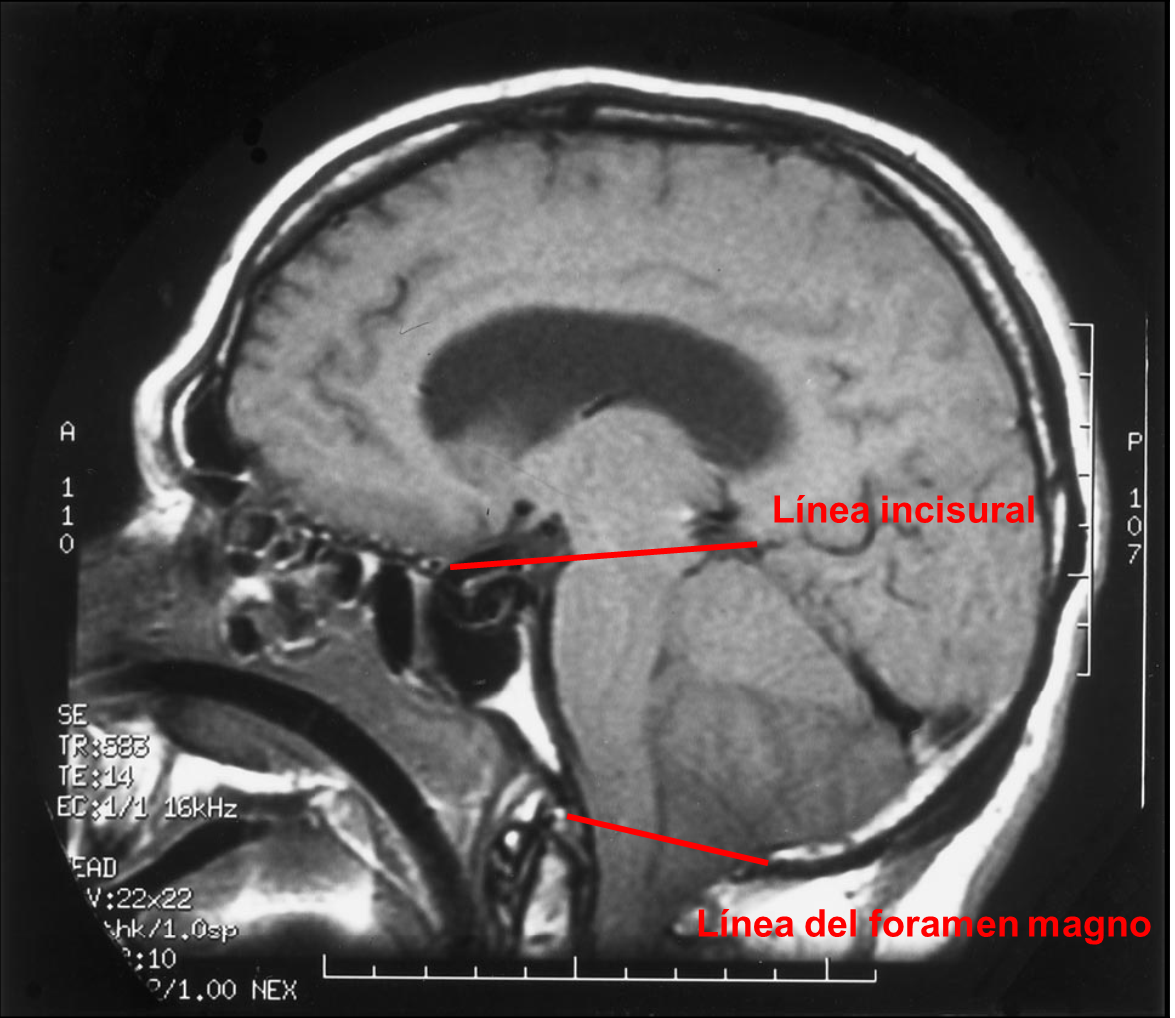

En la Imagen 4 señalo la línea incisural y la línea del foramen magno. La línea incisural es la línea dibujada desde la parte anterior del tubérculo selar hasta la confluencia del seno sagital inferior, seno recto y vena de galeno. En condiciones normales deja el mesencéfalo practicamente en su totalidad por debajo de la misma. La línea del foramen magno es la línea dibujada desde la punta inferior del clivus hasta el labio posterior del foramen magno. En condiciones normales esta línea se encuentra por debajo del bulbo raquídeo y deja las amigdalas cerebelosas por encima.